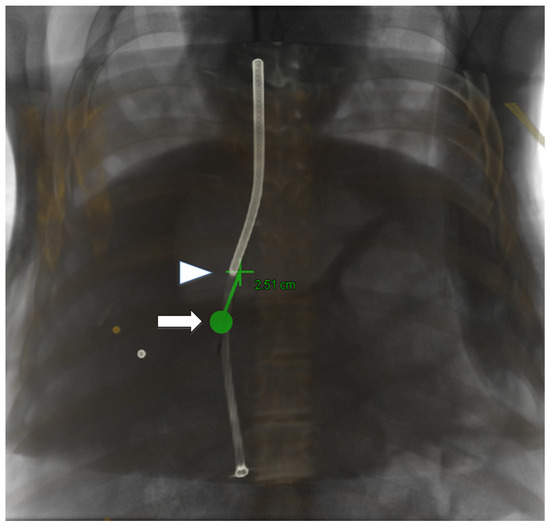

3.3. 3D Angiography-Guided TIPS Using CBCT/Angiography-Fused Images